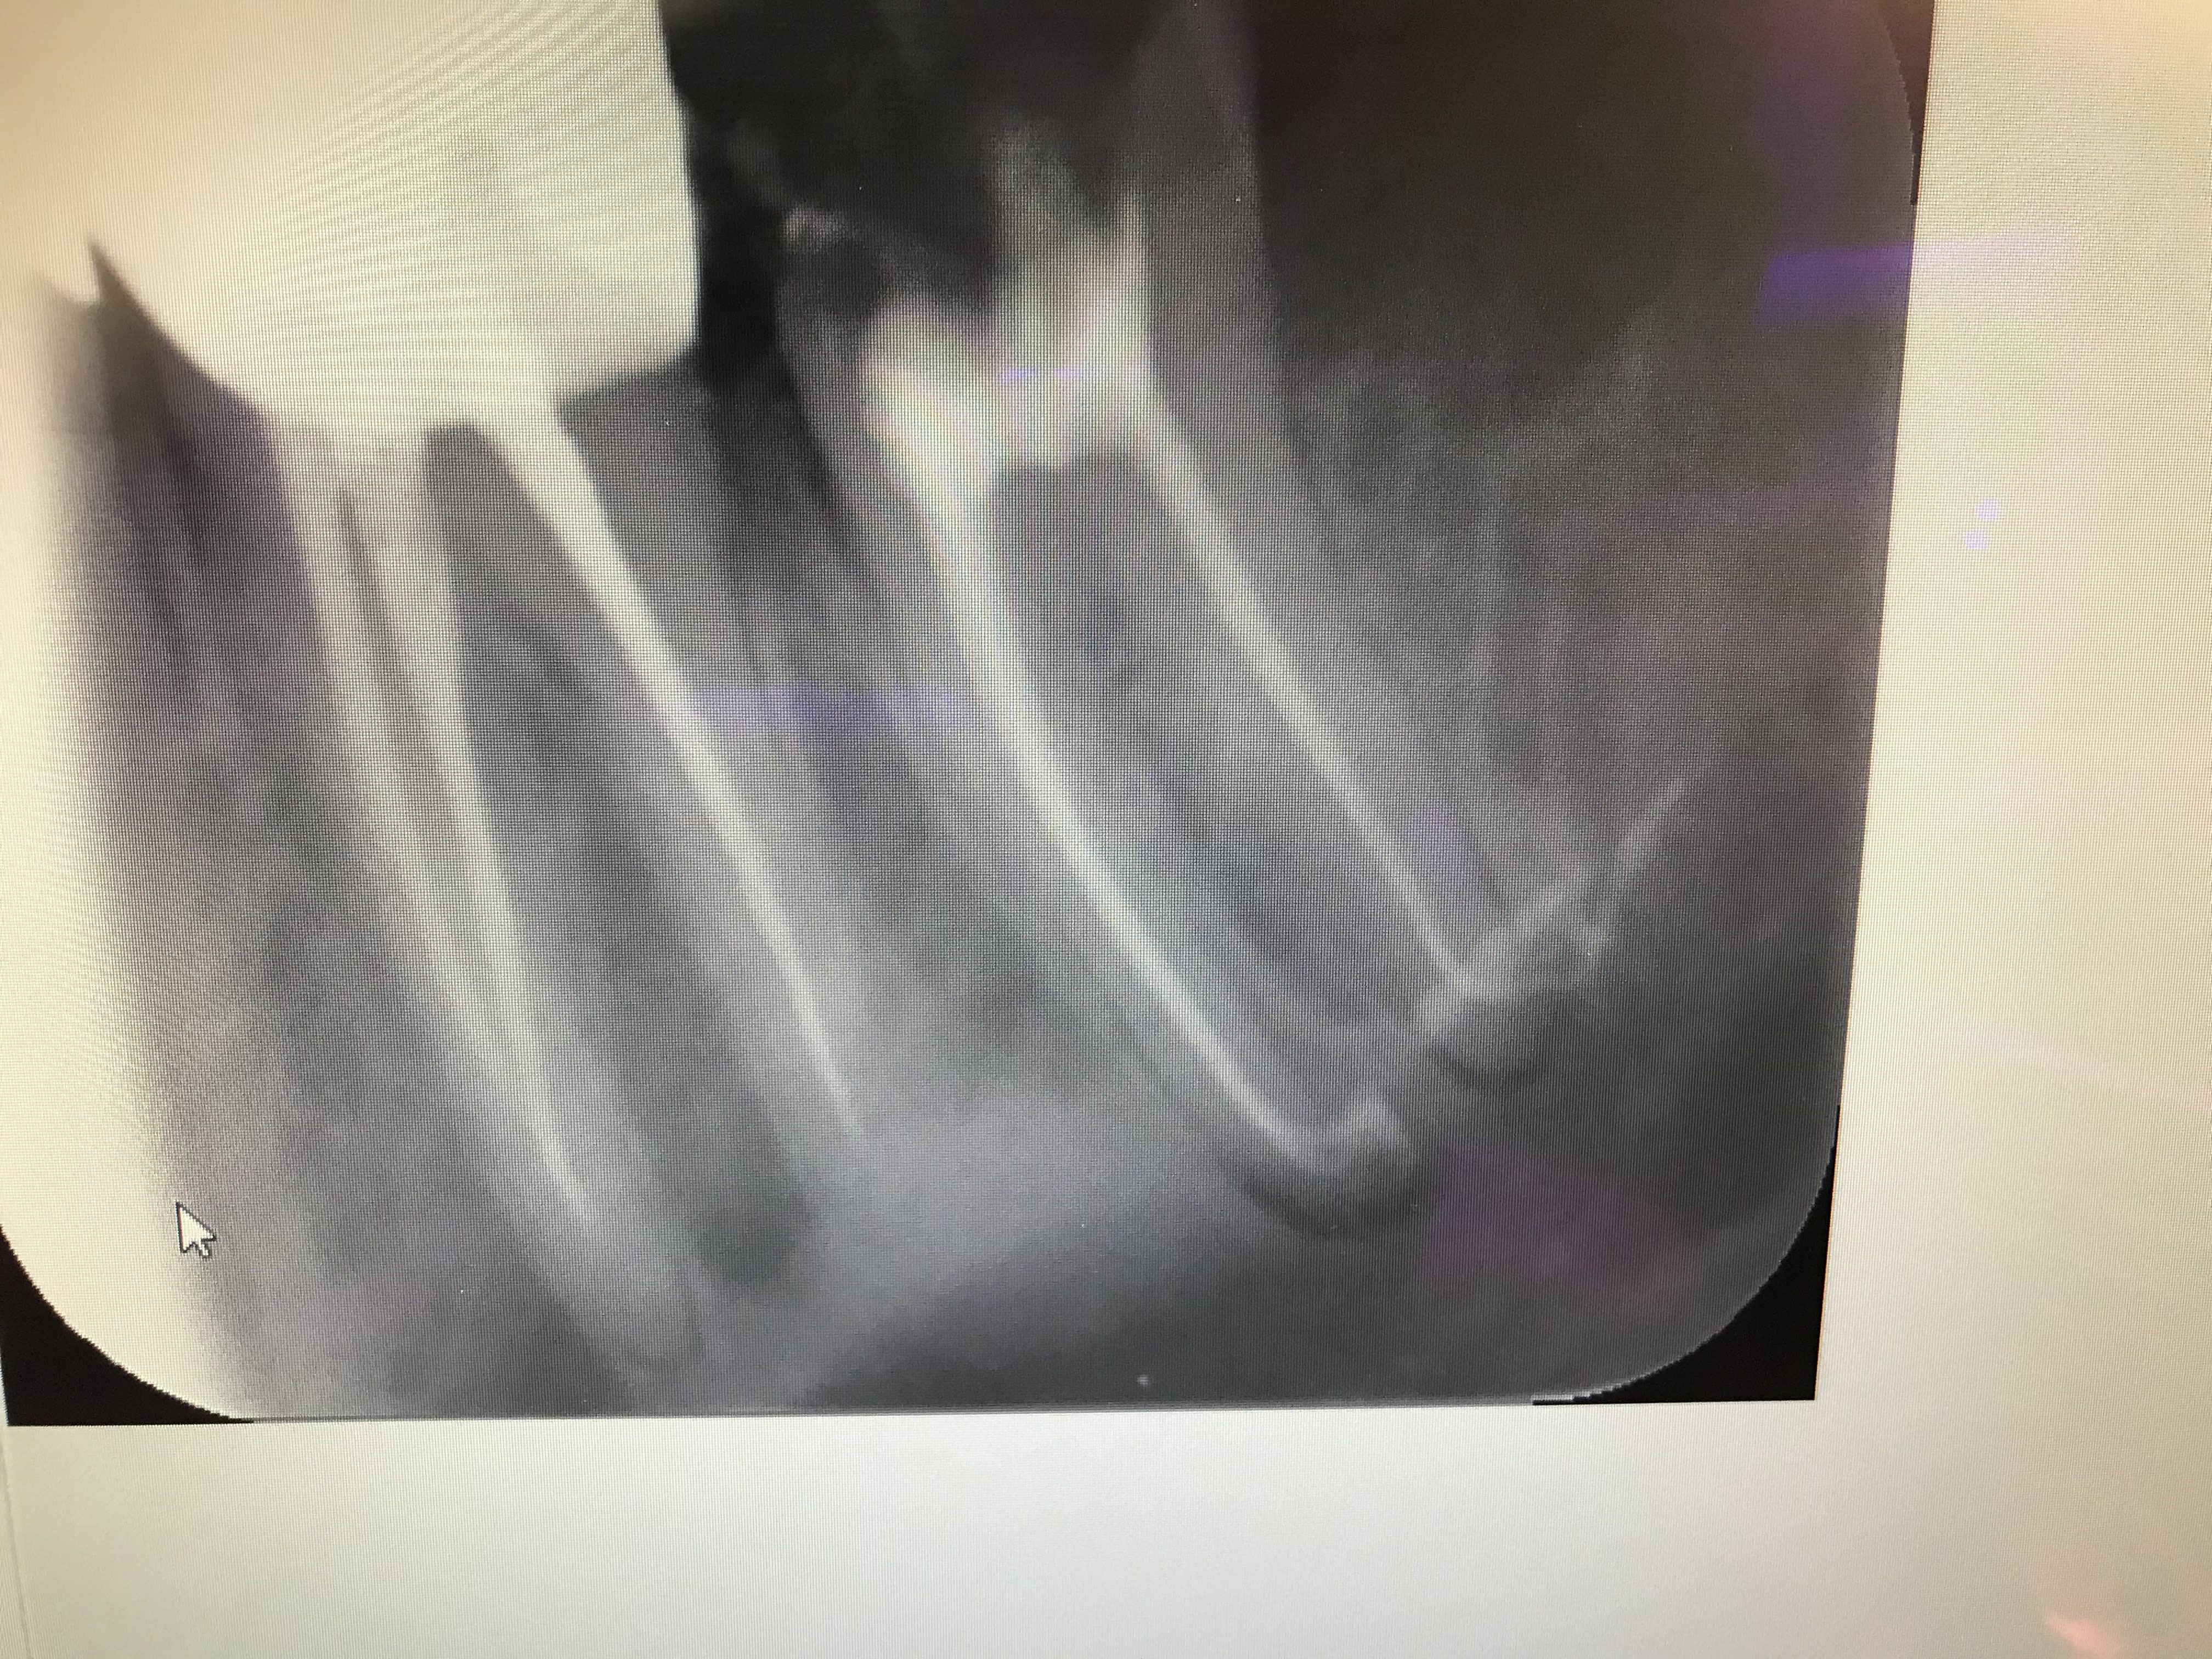

Regarde moi ça Vulpi, pour les cas complexes finalement je me rends compte que l’obturation à chaud rend bien des services . Celui-ci si je ne lui avais pas chauffé les miches, l’obturation n’aurait pas été faite à fond . Les racines font un angle à 90 deg au bout . Ça a fusé à 90 degrés indiquant que les courbures étaient extrêmes